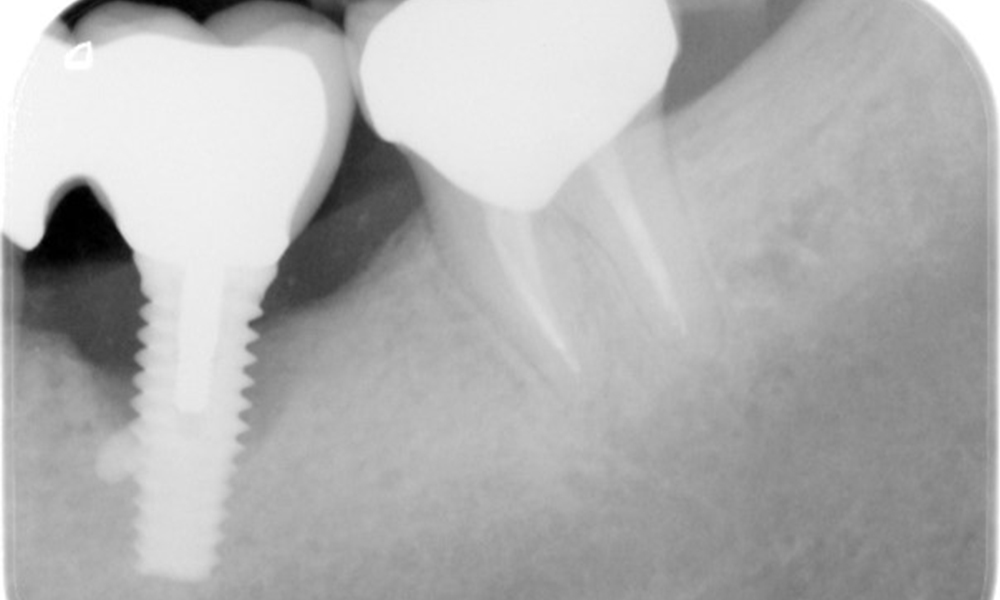

Der Patient zeigt keine besonderen anamnestischen Risikofaktoren mit spezifischen zahnmedizinischen Auswirkungen. Daher ist der aus der Mundgesundheit ermittelte Bedarf maßgebend. Hierbei zeigt sich am Implantat im 3. Quadranten ST von 5 mm und im Röntgenbild eine Zunahme des Knochenverlustes. Der Patient hat zudem eine aktuell stabile parodontale Vorerkrankung und zwei aktive initialkariöse Läsionen.

Röntgenaufnahme zeigt Verlauf des Knochenabbaus

"Die Röntgenaufnahmen zeigen den Verlauf des Knochenabbaus. OPG vom 29.06.2020 (links) und OPG vom 26.02.2024 (rechts)

Die Röntgenaufnahmen zeigen den Verlauf des Knochenabbaus im Bereich des Implantats Regio 36: ZF vom 11.02.2021 (links) und ZF vom 18.01.2024 (rechts)

OPG: 26.02.2024 ZF: 18.01.2024